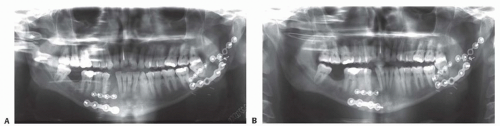

Plain x-ray films (facial series, panoramic) can be used for postoperative evaluation to identify an enlarging gap in the fracture line, presence of irregular radiolucency, and/or hardware loosening (FIG 1A, B).

Maxillofacial computed tomography (CT) with threedimensional formatting has become the imaging modality of choice for evaluation of the fracture site, extent of soft tissue infection, and associated osteomyelitis (FIG 1C-F).